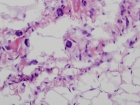

Patient is a 61 y/o male who presents w/ 3-month hx. of painless L. thigh mass; recent increase in size and pain; PMH: unremarkable

PE: L. thigh w/ large non-tender soft-tissue mass mid-thigh-prox. knee; NVI